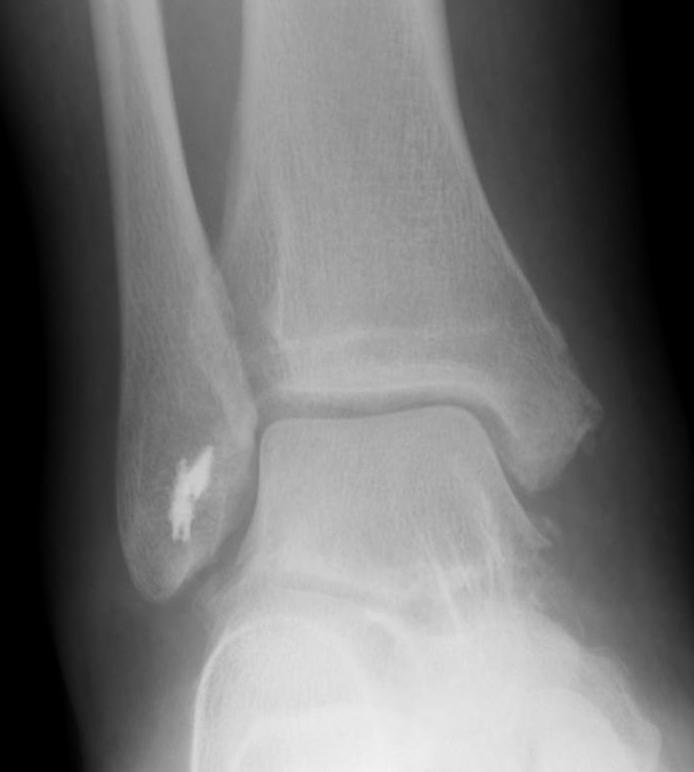

Xrays

Osteochondral lesions

Loose bodies

Stress Xrays

![]() |

ATFL tear

CFL tear